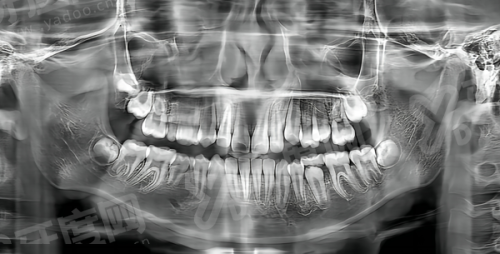

中喜口腔做种植牙不用“凭手感”,先通过3D CT扫描获取牙槽骨的精细数据,再用电脑模拟种植体的植入位置、角度和深度,末尾打印出定制化3D导板。手术时,医生跟着导板操作,能把误差控制在0.1毫米以内,比传统种植方法精细30%。像55岁男性下颌缺牙3颗、骨密度不足的情况,他们用“韩国登腾种植体+骨粉填充”方案,术后3个月骨结合良好,现在能正常吃排骨。

对于前牙缺失的患者,比如30岁女性想追求美观,他们用口扫仪直接扫描口腔,在电脑上设计全瓷牙冠的形状和颜色,做完后牙龈形态自然,和邻牙颜色几乎一致,别人根本看不出是种植牙。